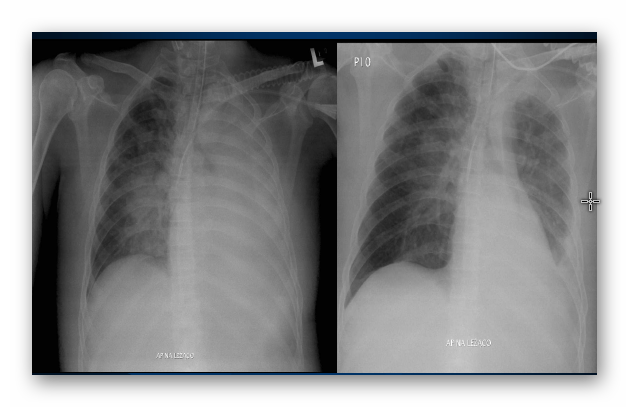

NIEDODMA

RTG

NIEDODMA PŁUCA LEWEGO

(WTÓRNA DO RAKA CENTRALNEGO PŁUCA LEWEGO)